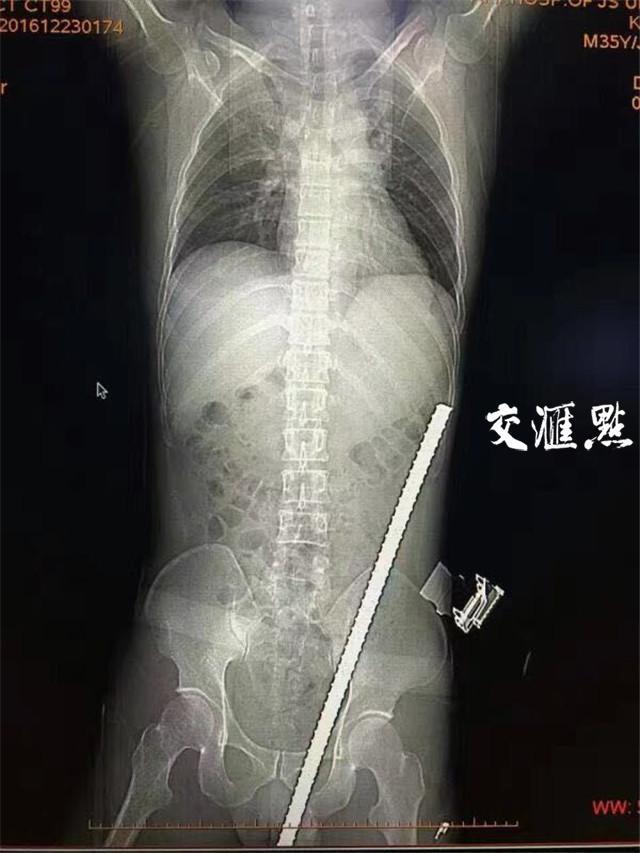

CT报告。

急诊医生做了初步检查后,一边联系泌尿外科、普外科会诊,一边赶紧将他送去CT室拍片。剪掉吴强的衣服后,医生发现,钢筋是从他的阴囊插进去的,根据工人描述的钢筋长度,医生做了初步估算,除去露在体外的一截,起码还有五六十公分长度的钢筋进入了吴强体内。

“看到CT报告,我们都稍稍松了口气”,江大附院泌尿外科副主任医师徐强说,从报告上看,钢筋是从阴囊左侧进入到了盆壁再进入了腹壁,初步看,并没有伤及什么脏器,这是最值得庆幸的。

采访中,徐强甚至开玩笑地说,这根钢筋犹如神助,可以说“长了眼睛”,如果是射击的话,可以说打出了10.9环的好成绩,虽然穿插到了腹壁,但通过的地方都是些软组织,是沿着膀胱边上穿上去的。

最让人感到惊心动魄的是,这根钢筋距离左侧髂血管仅有1点几公分的距离,“要知道,如果伤到了这根致命血管,势必造成大出血,病人往往都等不及送医。”